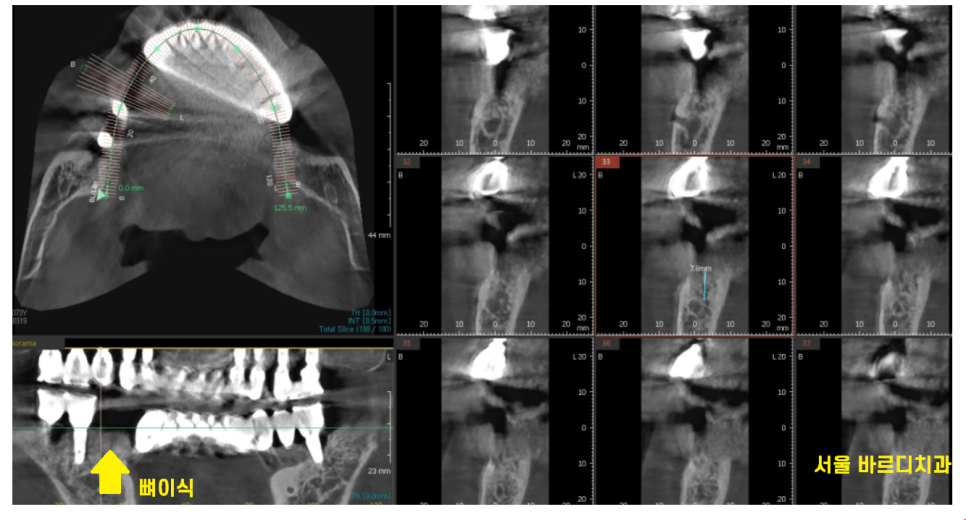

전신질환을 가진 환자분의 경우

덕소 치과에서 특히 신경쓰는데요.

해당 환자분도 내과 협진, CT 분석

철저하게 진행하였습니다.

24.03.19

그리고 발치 후 당일 뼈이식을 진행 후

뼈가 1차적으로 차면

그때 임플란트 수술을 진행하기로 하였습니다.